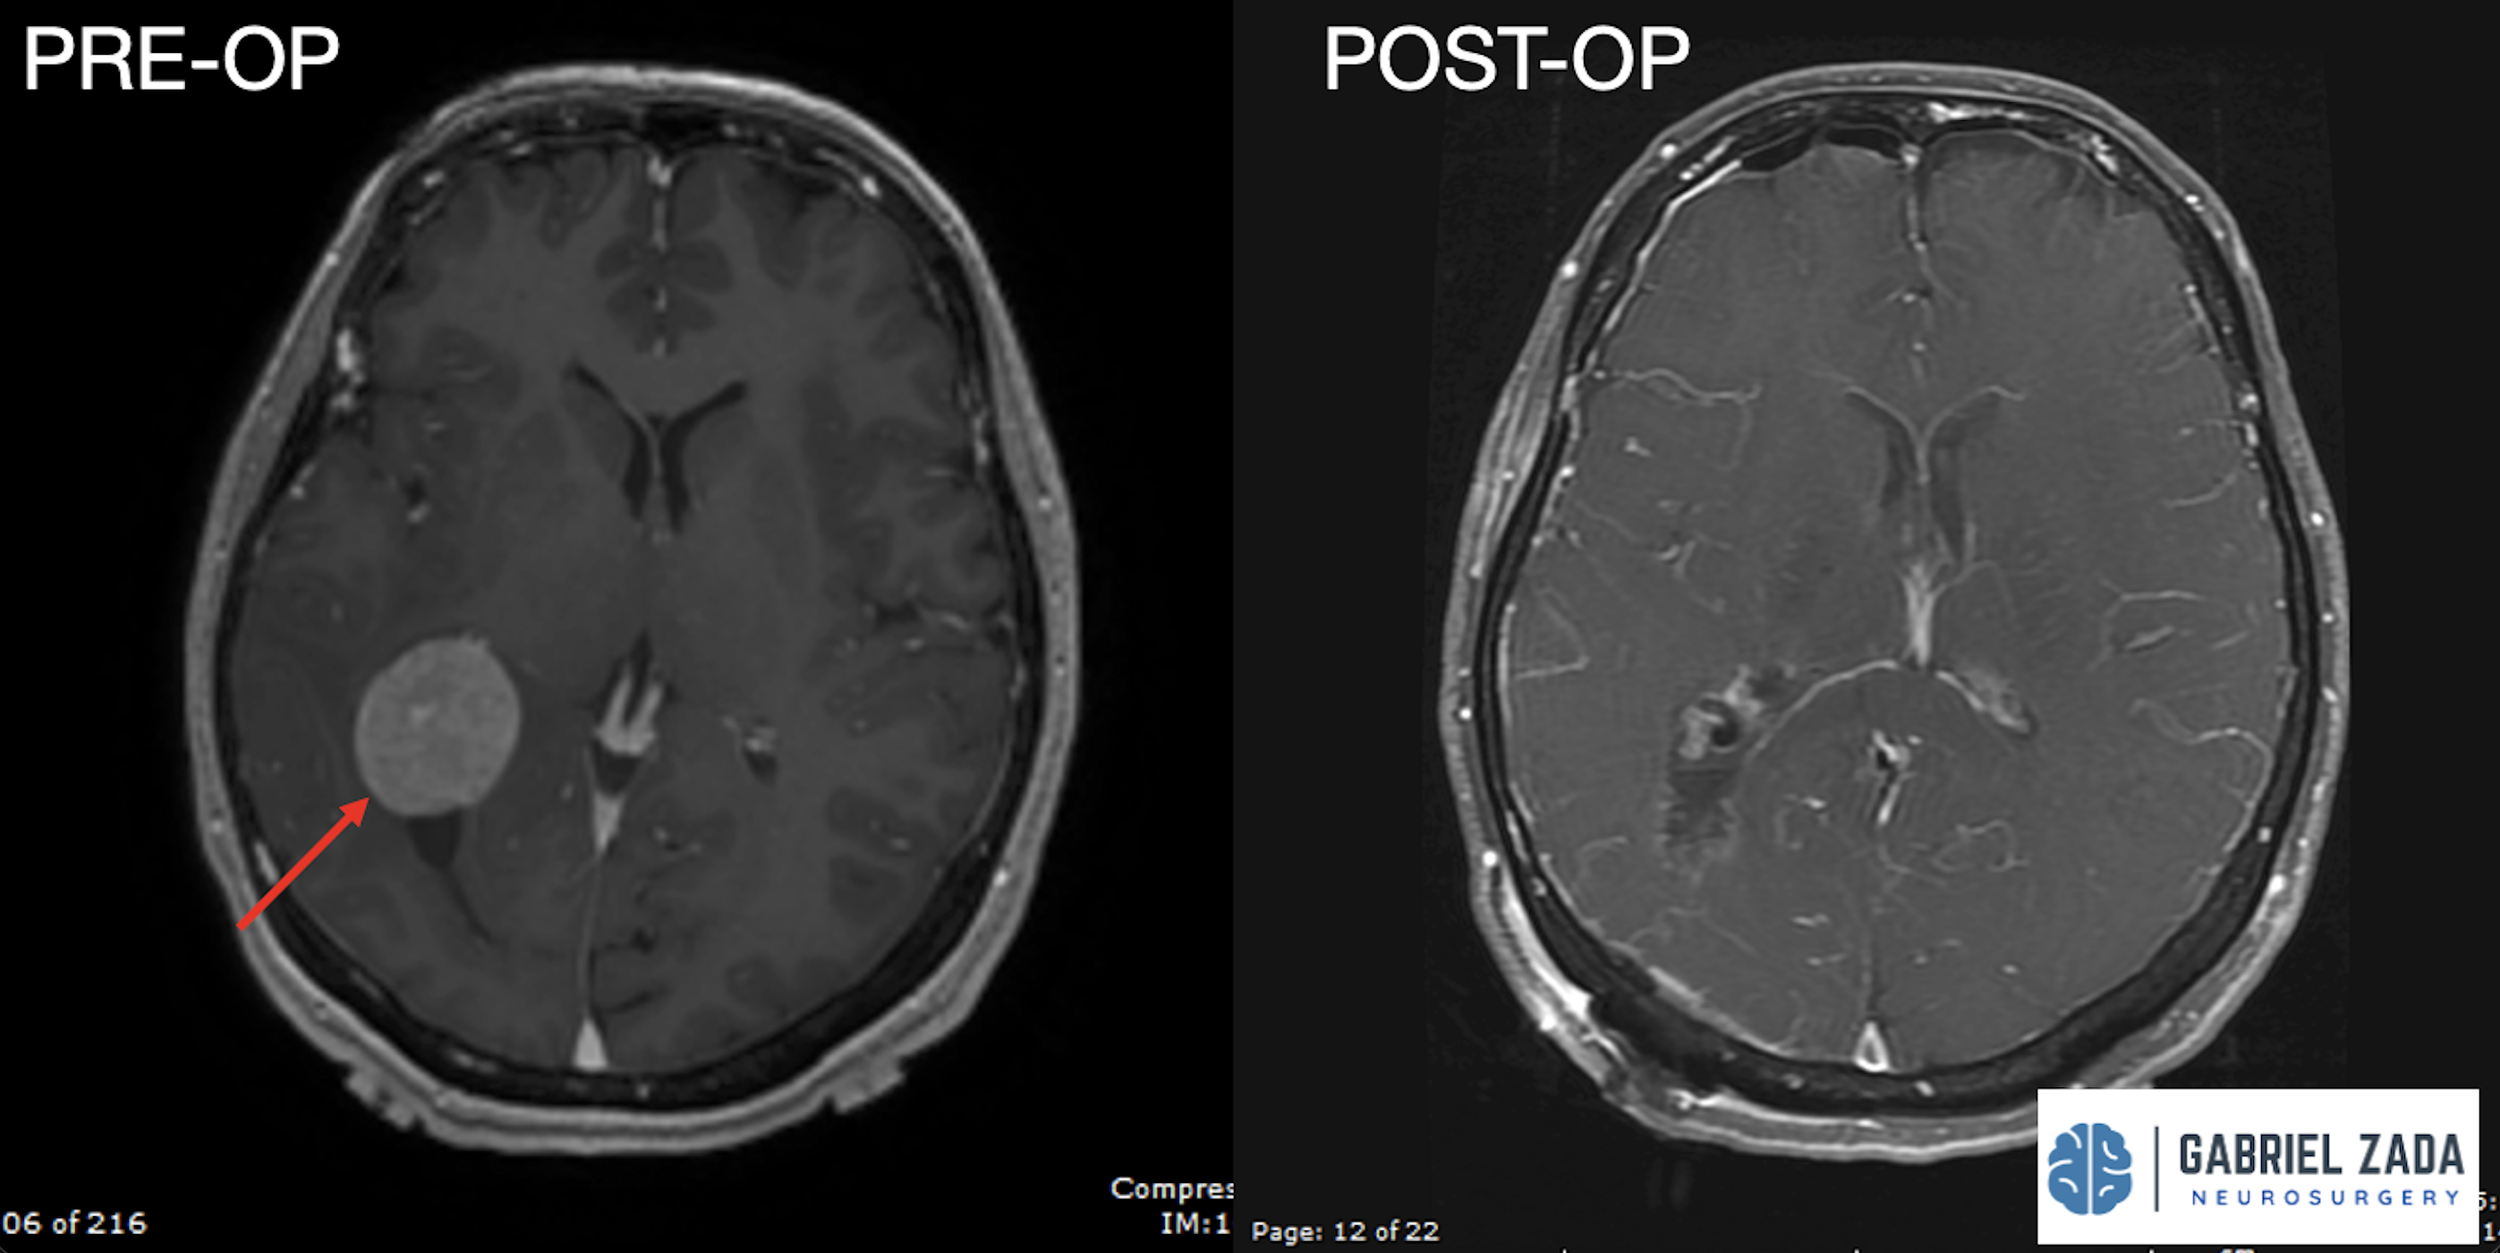

Explore this comprehensive gallery featuring pre‑ and post‑operative imaging of patients with skull‑base tumors treated by Gabriel Zada, MD, MS, FAANS, FACS. These cases highlight Dr. Zada’s expertise in advanced neurosurgical techniques and outcomes.

*Representative cases shown for educational purposes. All images de-identified. Individual results vary.